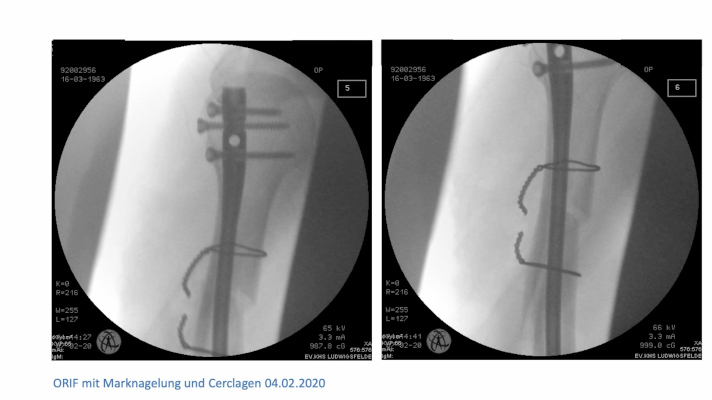

Case Presentation P. Niemeyer